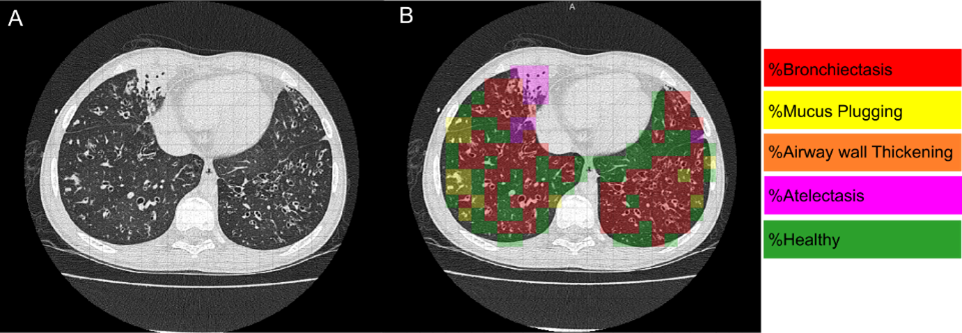

LungAnalysis has been working towards developing automated tools to quantify lung structural abnormalities. The lab has ongoing collaborations with Thirona B.V. (Nijmegen), a Dutch company specializing in cutting-edge artificial intelligence strategies for quantitative lung imaging. Together, LungAnalysis and Thirona co-developed a fully automated, sensitive system to measure bronchial widening, bronchial thickening, mucus plugging, and trapped air on chest CT. The algorithm has been integrated into Thirona’s certified software platform, LungQTM, which is installed on the virtual platform DRE at LungAnalysis, Erasmus MC. Current work on the validation of the automated tools is ongoing in a wide range of lung diseases, including CF.